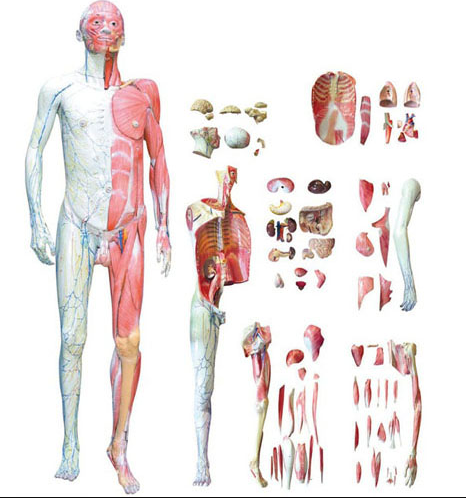

■ 尺寸:自然大,260×180×200mm;

■ 部件:2部件;

■ 功能:顯示男性骨盆和盆底諸肌肉。男性(xìng)骨盆示左右髖骨、骶(dǐ)骨、尾骨(gǔ)和它們的連接。顯示大骨盆、小骨盆和骨盆入口、骨盆出口。顯示坐骨大孔、坐骨小(xiǎo)孔、閉孔、髖臼、坐骨結節等。在此(cǐ)基礎上(shàng)顯示盆腔內膀胱、直腸、肛提肌(恥尾肌、髂(qià)尾肌、恥骨直腸肌)肛提肌腱弓,尾骨肌和閉孔內肌。盆(pén)腔外部顯示男性外陰諸結構(gòu),模型還(hái)示骶棘韌帶、肛門(mén)外括約肌等;盆(pén)腔外部還顯示尿生殖三角肌,淺層包括會陰淺橫肌、球海綿(mián)體肌和坐骨海綿體肌;深層包括(kuò)會陰深橫肌、尿道膜部括約肌等結(jié)構(gòu);

■ 材質:進口(kǒu)環保PVC材料,進口環保油漆。